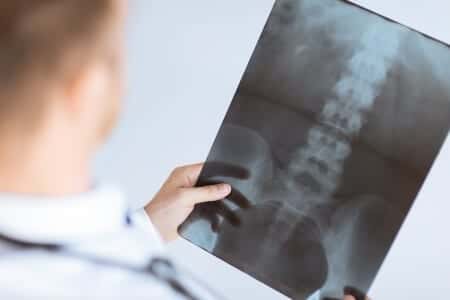

This case involves a male patient in Hawaii who was prompted to seek medical attention for severe and sudden back pain. He indicated to the internist who saw him that the pain began in his lower spine and was radiating down the back of his left leg. The physician diagnosed him with a likely spinal issue related to a bulging disk, and prescribed muscle relaxants as well as painkillers and, after an MRI was administered, was discharged him home. Over the course of the next few days, the patient was not given any updates on the status of his MRIs, despite repeated calls to the hospital. On the fifth day, the patient received a call from the hospital and was told to go to the nearest emergency room for immediate treatment. On arrival, the patient listed his complaints as radiating pain in his back which had grown progressively worse, as well as incontinence, numbness, and the inability to lay down comfortably. An MRI demonstrated that the patient was suffering from multilevel disk and joint disease, and was eventually diagnosed with cauda equina syndrome and herniated disc disease.